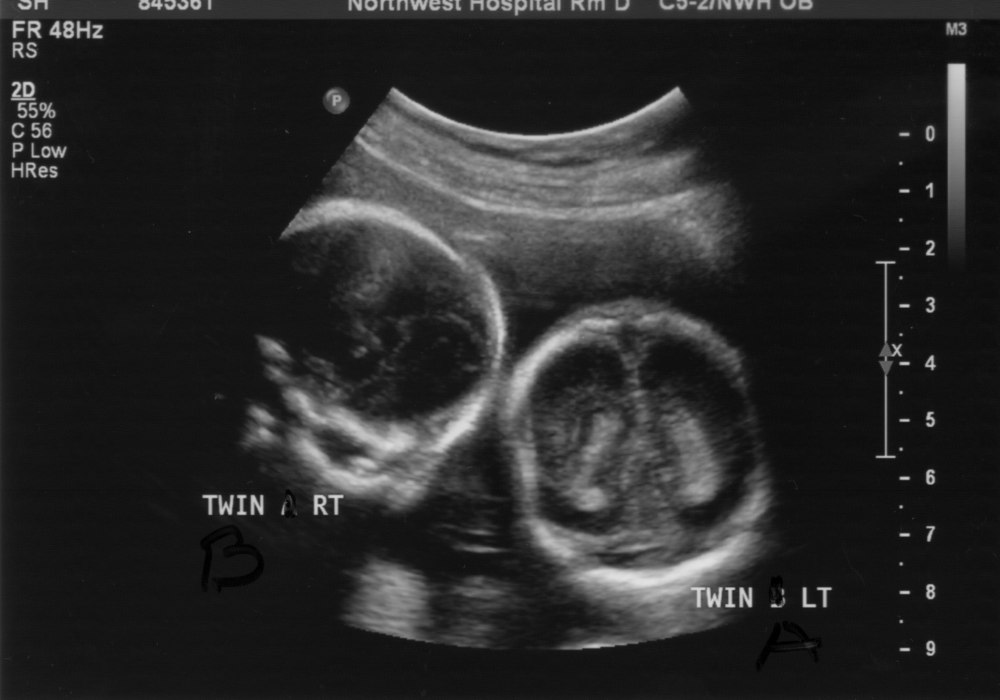

twin ultrasound of 10 1/2 week twins Twins ultrasound, How to have twins, Ultrasound How Many Ultrasounds For Twins How many ultrasounds do you have during a twin pregnancy? If you’re expecting twins or more, you will be offered the more common ultrasounds including: A basic ultrasound takes about 15 to 20 minutes. Most people may only receive one or two ultrasounds during pregnancy. Oct 23, 2024 at 4:51 pm. As a twin mom, the general rule is that. How Many Ultrasounds For Twins.